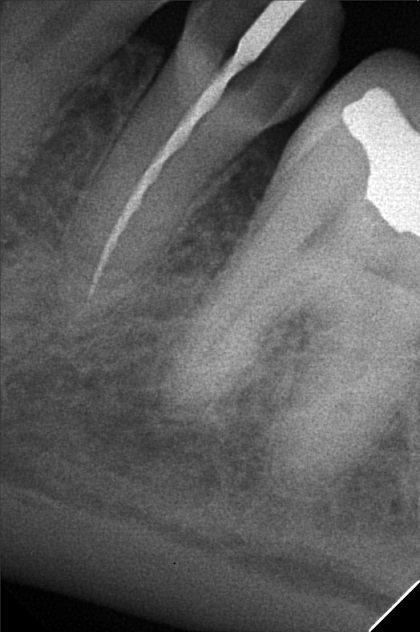

- 9/24/22 - Check up & Xray 10/01/22 - RCT 18mm , formacresol #35 10/08/22- RCT 17mm, campenol 10/15/22- 17.5MM PULP DEVITALIZER PAD done 11/05/22- Zirconia/LC 16 11/19/22- OP/Install Of Crowns